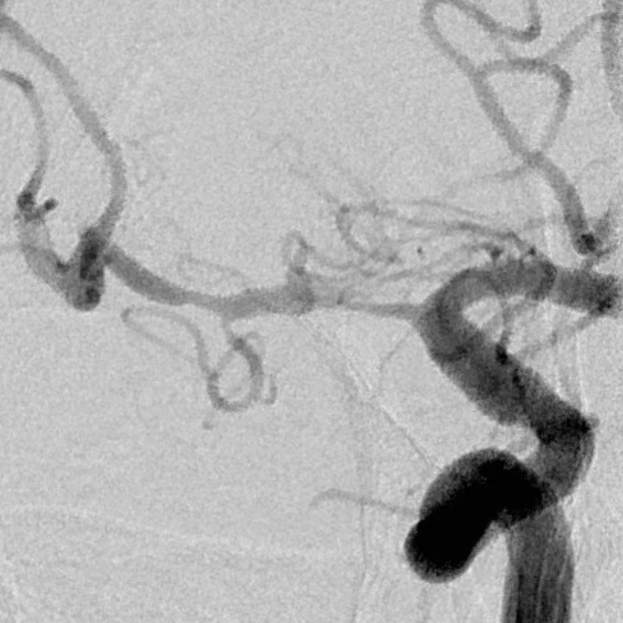

​2、第二个患者:我们给予一期外科干预后,一个月后检查发现,狭窄的部位和术后即刻相比是稳定的,二期安全的植入支架,血流完全恢复正常,顺利出院;

术前

术后即刻

术后一个月随访稳定,给予支架植入,血流恢复正常,分支血管保留良好